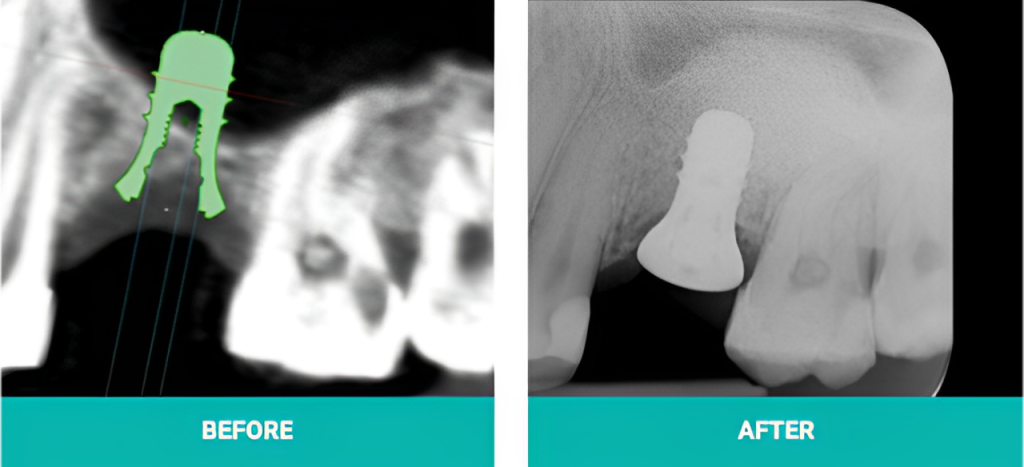

Before the surgery, you will have a periodontal consultation in which the periodontist will perform an analysis to determine the size and shape of the new gum line that is appropriate for your mouth.

During a crown lengthening treatment, a periodontist or dentist will remove excess gum tissue from your mouth.

The procedure will depend on the technique that is selected for you based on your individual needs. Three of the most common techniques are: